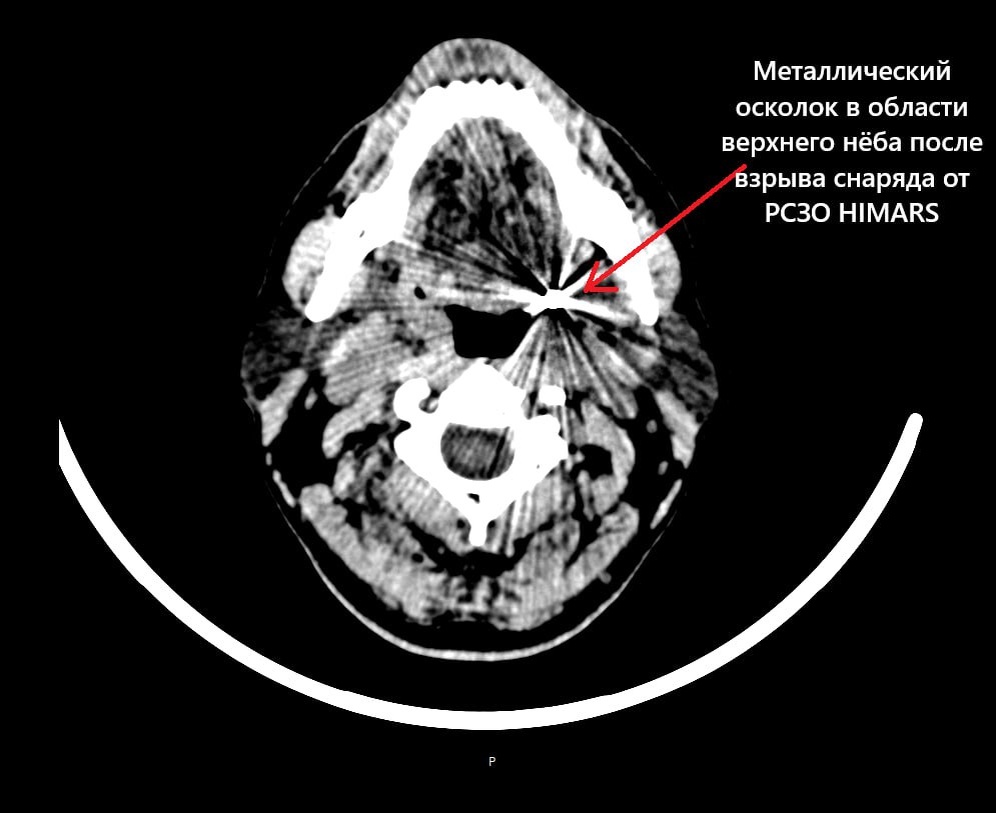

КТ головы пациента с осколком в области верхнего нёба.

На КТ-снимке — металлический осколок в области верхнего нёба (определяется как артефакт с лучистой структурой) у бойца, получившего ранение при взрыве двух снарядов от РСЗО HIMARS. Всего в тело попало 14 осколков: в руку, ногу и голову. Несмотря на массивное поражение, головной мозг не был задет — осколок остановился в нескольких миллиметрах от жизненно важных структур. Однако боец потерял правый глаз. Этот случай — напоминание о специфике ранений в современной войне, в основном осколочных.